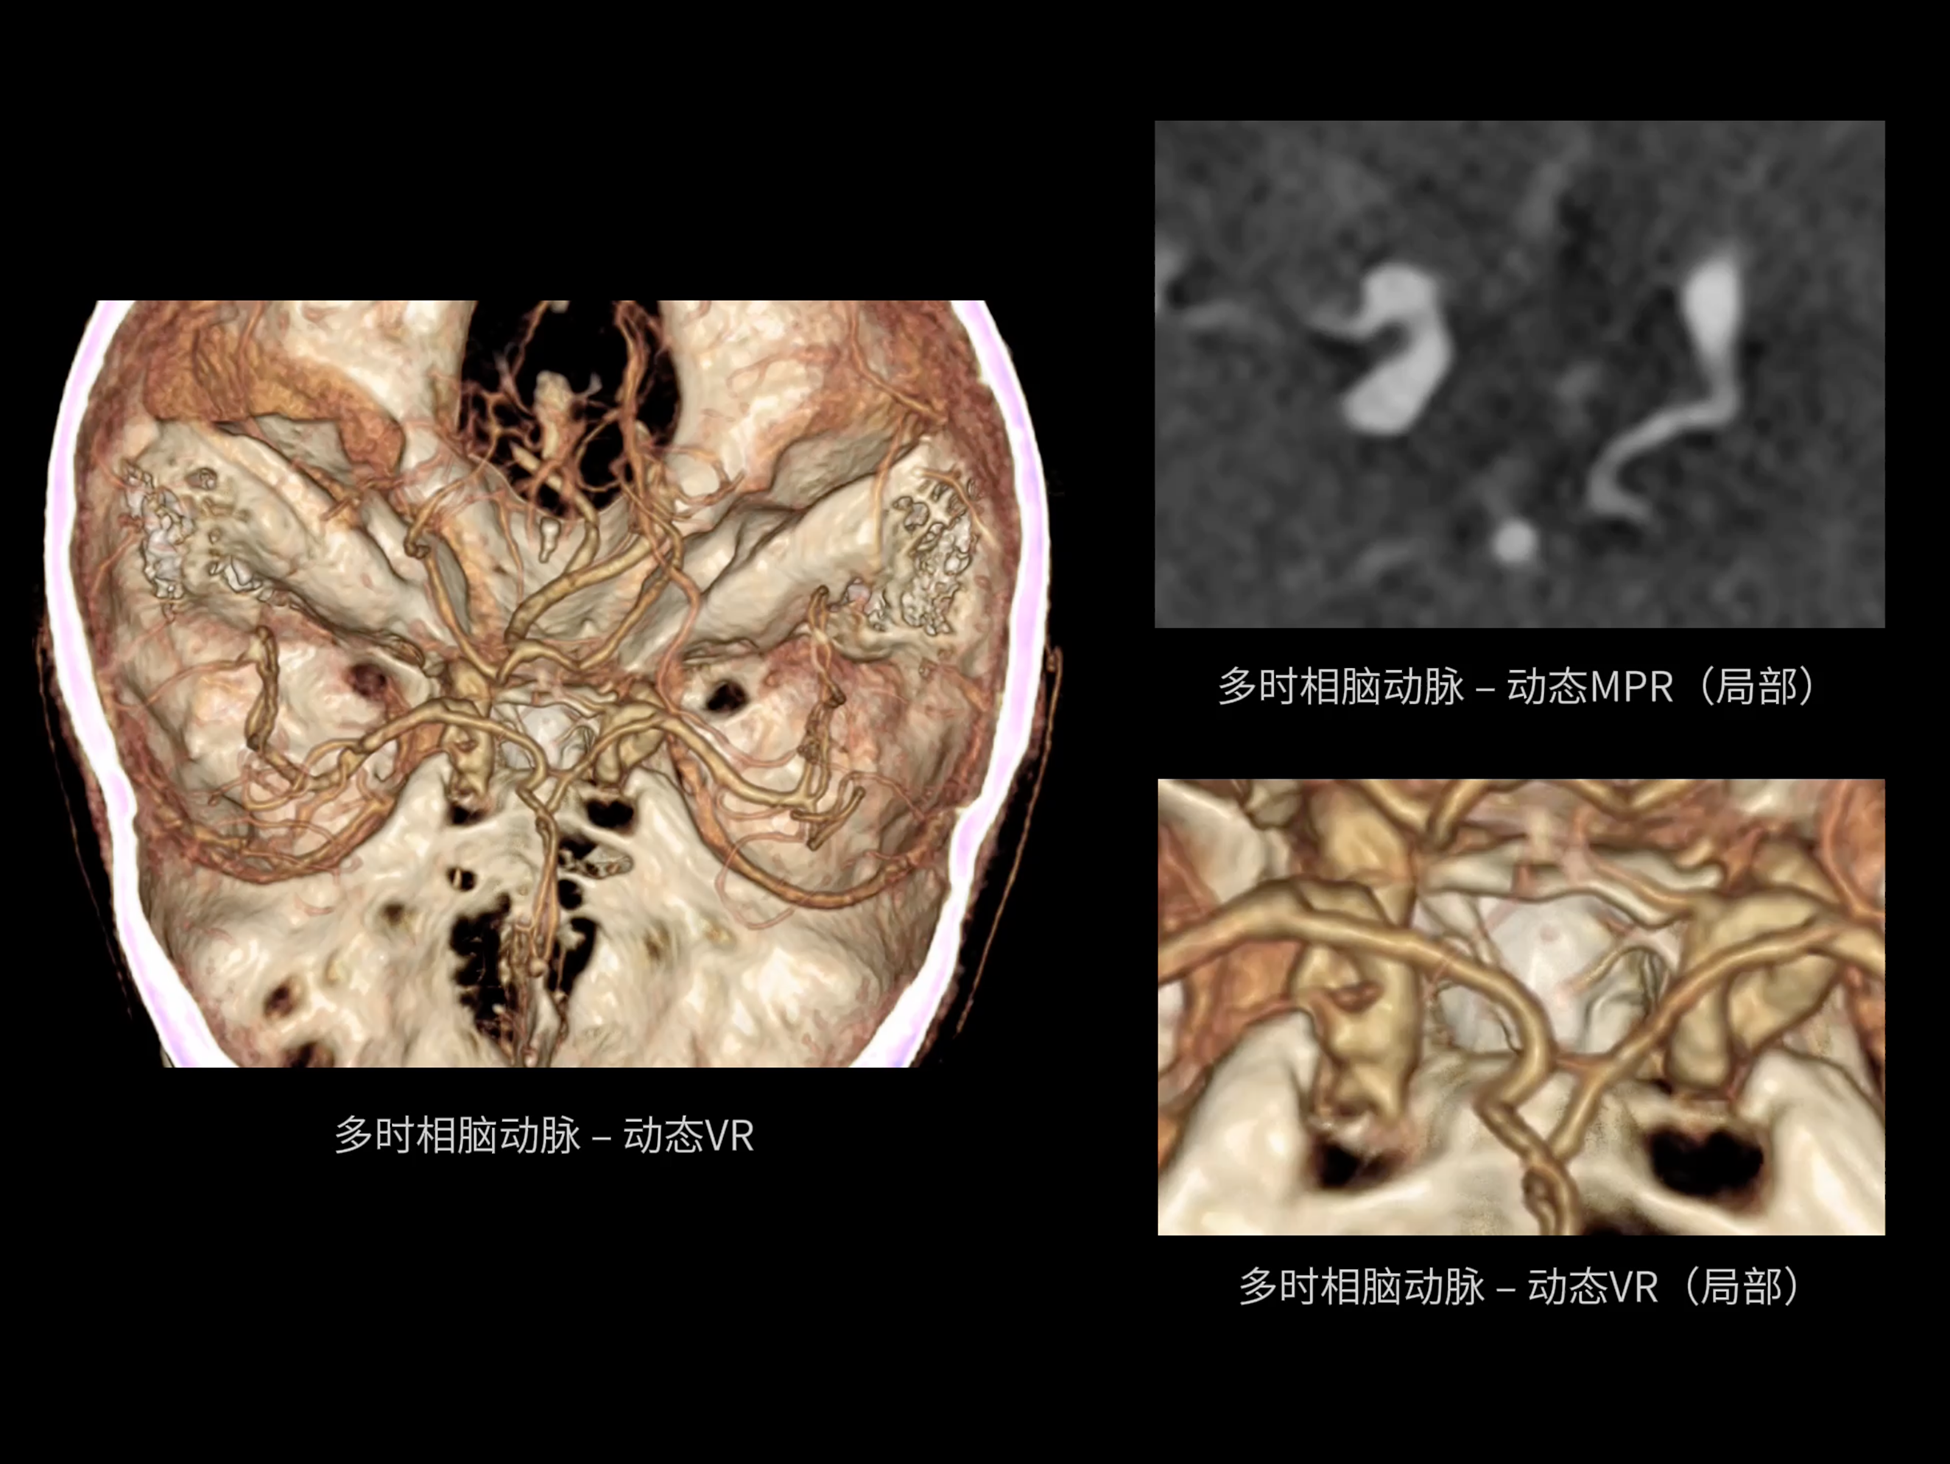

CardioCapture 2.0 通过“识别–追踪–建模–校正”的完整流程,精准分割心脏结构,动态追踪运动轨迹,并构建多时相运动场,最终实现冠脉、瓣膜、心肌及心室结构的同步校正,清晰洞见每一次心跳细微变化,真正将心脏动态掌握于毫秒之间。

CardioCapture 2.0 在目标时相前后重建多时相影像,通过深度学习网络精准提取冠脉中心线,进而建立时相间运动模型,实现对冠脉分段图像的精准运动校正。

CardioCapture 2.0 可对心肌、瓣膜及心室等结构进行同步运动校正。基于深度学习的心脏精细分割,实现了更完整的心脏全局信息提取,能有效抑制全心运动伪影,显著提升心脏细节的清晰度与诊断可靠性。

冠脉运动校正

全心结构运动校正